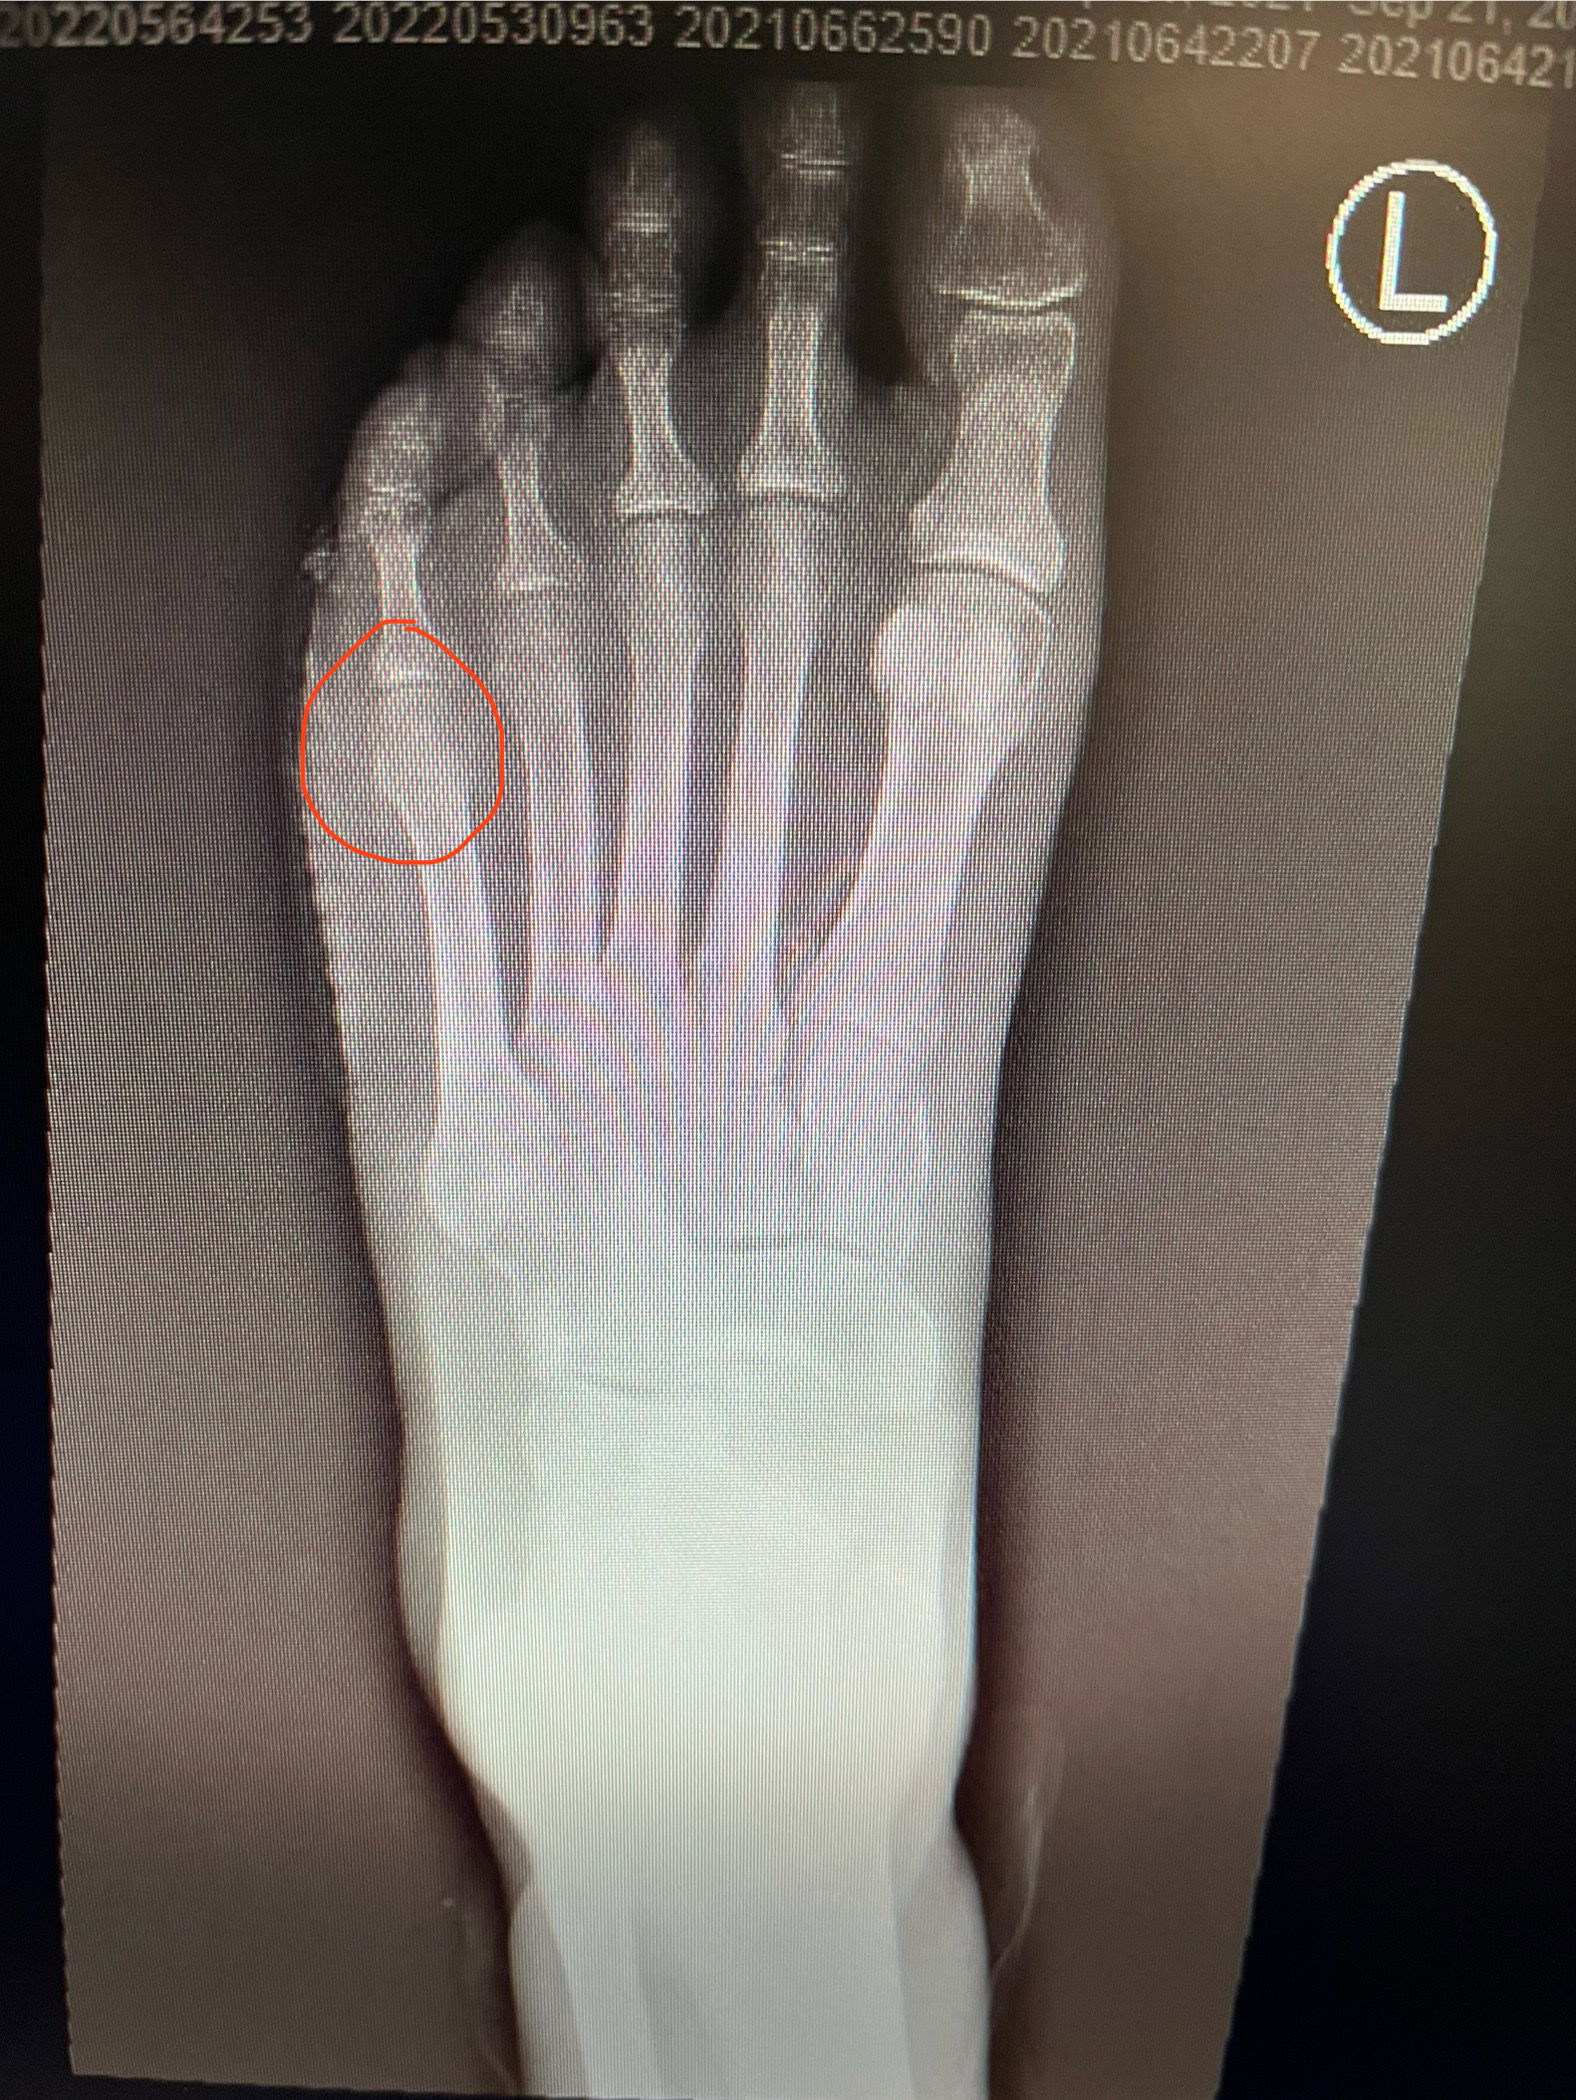

זהו פצע קלאסי שיושב מתחת לראש עצם המסרק (מסומן בעיגול אדום למטה)

הפצע נוצר כתוצאה מלחץ של העצם כנגד הקרקע שגורם לפגיעה ברקמה הרכה ולבסוף פצע. זו גם הסיבה שלמרות שהפצע החלים בעבר, הוא נפתח מחדש.

בבדיקה, הקוטר של הפצע אמנם היה קטן, אבל הוא הלך עמוק עד לעצם. מחקרים רבים הראו שברגע שיש בדיקה חיובית של נגיעה בעצם (positive probe to bone test) הסיכוי לזיהום בעצם הוא מאוד גבוה. מבחינתי, כשאני רואה פצע כזה, זה כמו פצצה מתקתקת שיכולה להתלקח בכל רגע ולהסתיים בזיהום רציני וכריתה של האצבע ואפילו יותר.